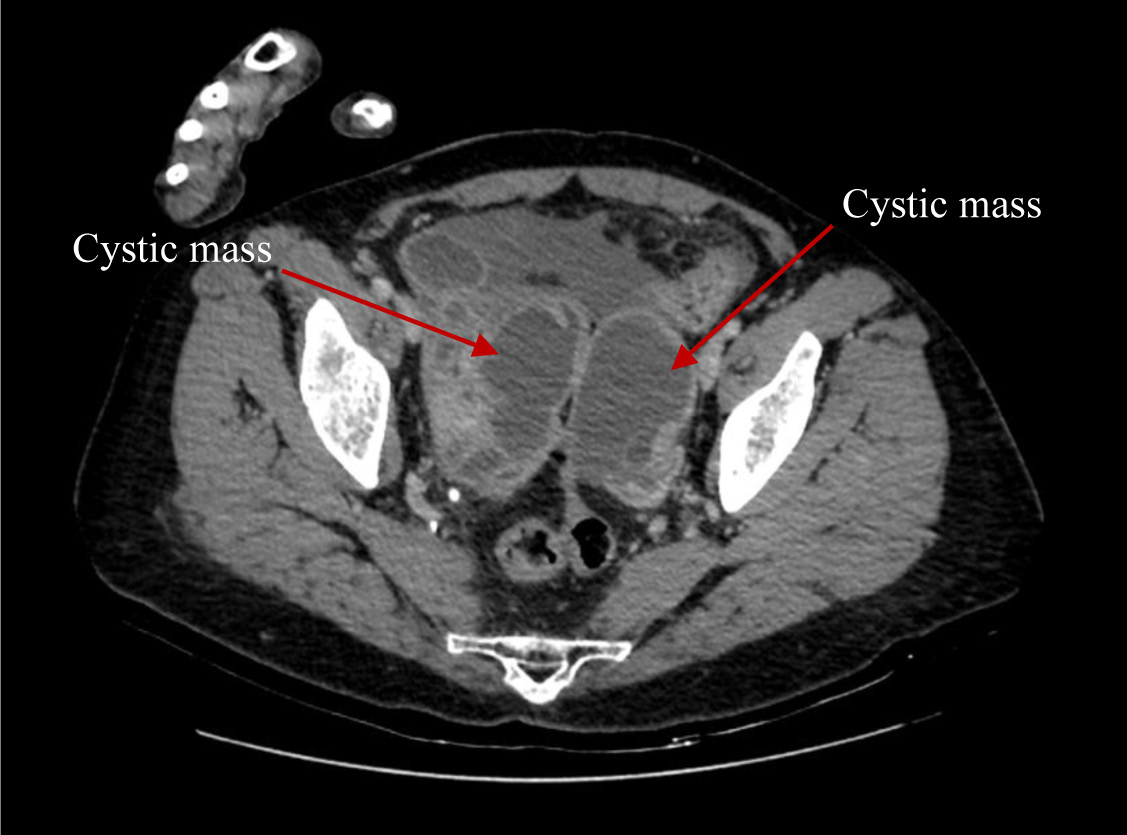

Cystic masses, measuring 6.8 × 6.6 cm in the right adnexa and 7.8 × 5.1 cm in the left adnexa were detected during transvaginal sonography. Computer tomography (CT) of the abdomen and pelvis (Figure 1 and 2) demonstrated abnormal changes in both ovaries. Size of multiloculated cystic lesion in the right ovary was 6.8 × 6.6 cm and 7.8 × 5.1 cm in the left ovary. A small amount of free fluid was found in the pelvic cavity along with thickened pelvic peritoneum.

Figure 2. CT report of abdomen and pelvis. Cystic masses in both ovaries (red arrows).